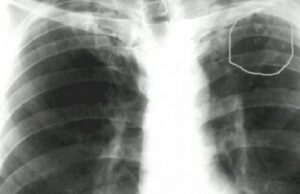

Выявление первичного туберкулезного комплекса (ПТК)

Раннее выявление синдрома первичного туберкулеза — сложная задача даже для современной медицины. Заболевание не имеет специфических симптомов, а симптомы считаются признаками острой респираторной инфекции или пневмонии. Первые подозрения на ошибочный диагноз и возможное наличие туберкулеза появляются только после нескольких недель безуспешного лечения антибиотиками от «пневмонии». Общая информация Первичный туберкулезный комплекс (ПТК) — один из клинико-морфологических …